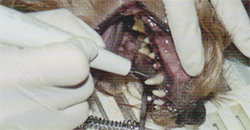

Zahngesundheit

- Gebisskontrolle bei Welpen und Zuchttieren

- Zahnsteinentfernung per Ultraschall und Politur

- Zahnkorrekturen, -füllungen und Zahnkronen